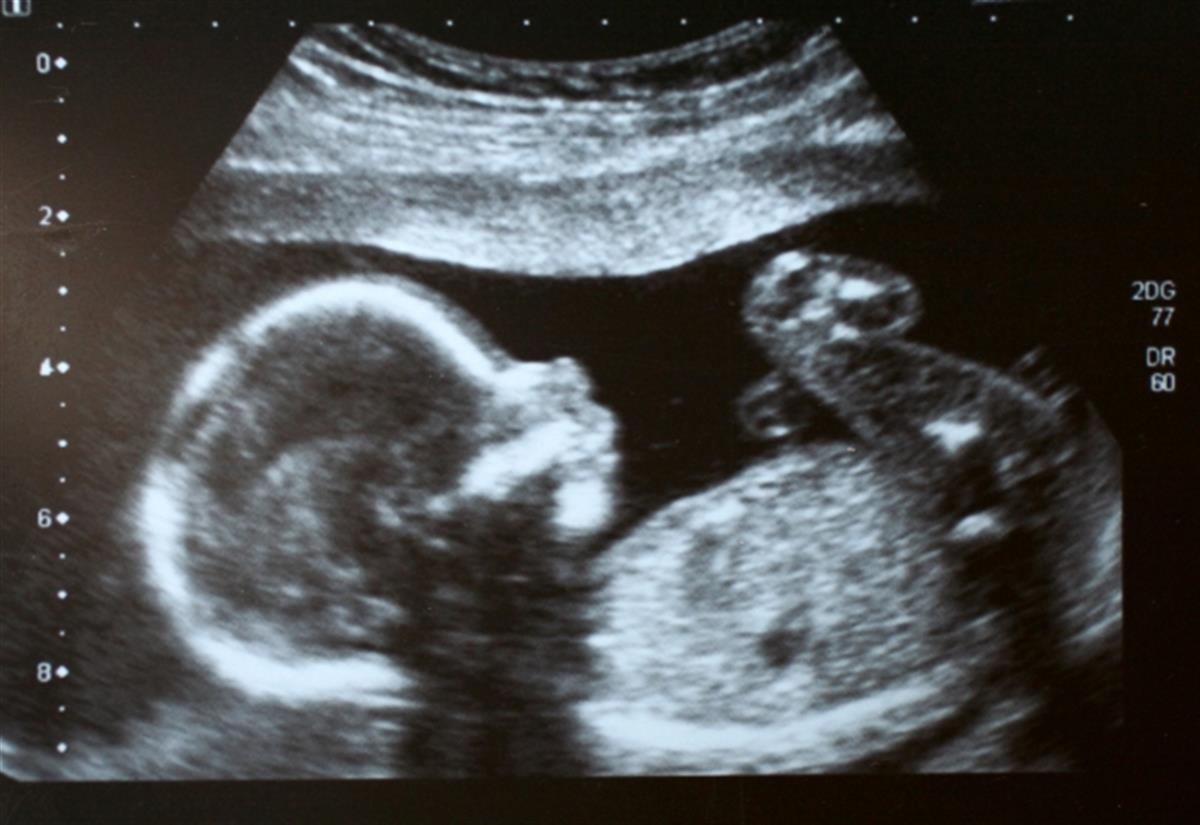

胎儿(图源:《太阳报》)

当这位母亲怀孕34周时,波士顿儿童医院的医生为上述胎儿进行了手术。医生使用超声波引导一根长针穿过母亲的腹部,进入胎儿大脑中动脉受影响的部位,然后将一种物质注入其中。